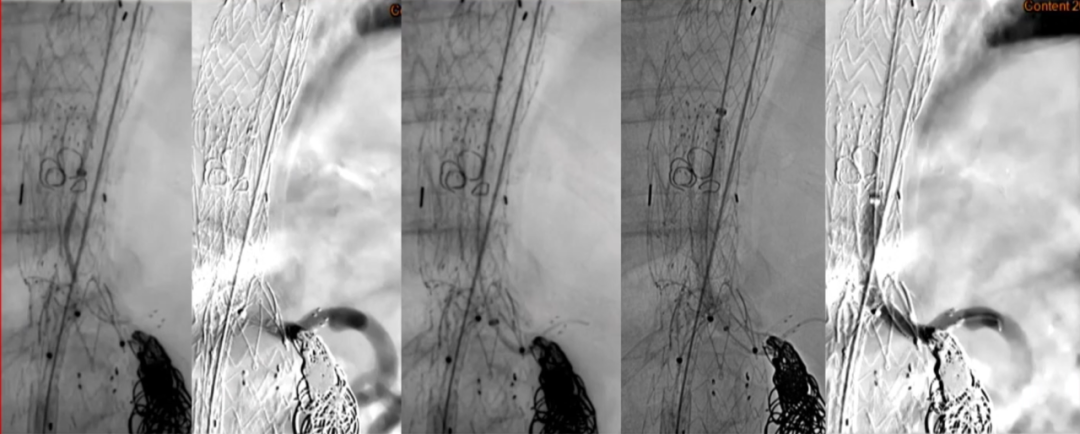

35-14-140mm分叉型支架,缝制内分支并固定,RRA、LRA:5mm Viabahn,CA、SMA:7mm Viabahn

分支预置导丝,回装支架

超选SMA,桥接8-100mm Viabahn,内衬8-60mm Absolute裸支架

超选CA,桥接8-100mm Viabahn

超选RRA烟囱支架,桥接6-100mm+6-50mm Viabahn

超选LRA烟囱支架,桥接6-100mm Viabahn

右侧:16-16-140mm Excluder髂腿;

左侧:16-16-120mm Excluder髂腿